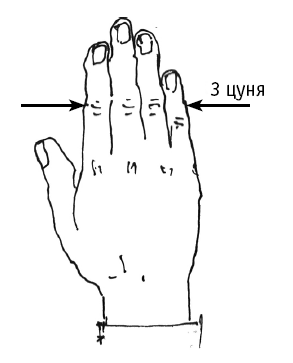

Чтобы отмерить 3 цуня, складываем 4 сомкнутых пальца выпрямленной (правой или левой) ладони (рис. 2).

Чтобы отмерить 3 цуня, складываем 4 сомкнутых пальца выпрямленной (правой или левой) ладони (рис. 2).